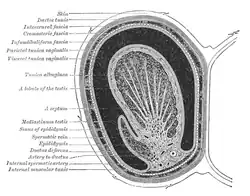

The testes are covered by a tough fibrous shell called the tunica albuginea.[5] Under the tunica albuginea, the testes contain very fine-coiled tubes called seminiferous tubules.[5] The tubules are lined with a layer of cells (germ cells) that develop from puberty through old age into sperm cells (also known as spermatozoa or male gametes).[5] The developing sperm travel through the seminiferous tubules to the rete testis located in the mediastinum testis, to the efferent ducts, and then to the epididymis where newly created sperm cells mature (spermatogenesis).[6] The sperm move into the vas deferens, and are eventually expelled through the urethra and out of the urethral orifice through muscular contractions.[6]

Within the seminiferous tubules, the germ cells develop into spermatogonia, spermatocytes, spermatids and spermatozoa through the process of spermatogenesis. The gametes contain DNA for fertilization of an ovum.[7] Sertoli cells – the true epithelium of the seminiferous epithelium, critical for the support of germ cell development into spermatozoa. Sertoli cells secrete inhibin.[8] Peritubular myoid cells surround the seminiferous tubules.[9]

Between tubules (interstitial cells) exist Leydig cells[10] – cells localized between seminiferous tubules that produce and secrete testosterone and other androgens important for puberty (including secondary sexual characteristics like facial hair), sexual behavior, and libido. Sertoli cells support spermatogenesis.[11] Testosterone controls testicular volume.

Layers

Many anatomical features of the adult testis reflect its developmental origin in the abdomen. The layers of tissue enclosing each testicle are derived from the layers of the anterior abdominal wall.[1] The cremasteric muscle arises from the internal oblique muscle.[1][18]